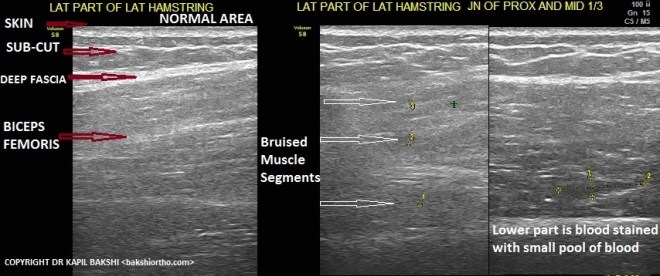

Muscle trauma and Bruising